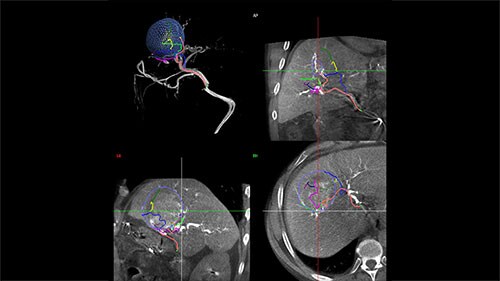

Step 2 – Reach

Based on these images, EmboGuide’s automatic feeder detection can detect significantly more feeding vessels than the current treatment standard of DSA.² ⁴

Live Image Guidance then supports selective or super-selective approaches to the embolization target.